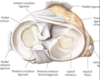

Hip Joint

& ligaments

Hip Joint

The hip joint is a ball-and-socket synovial

joint between the head of the femur and

the acetabulum of the coxal bone.

Head of femur & acetabulum are

connected by ligaments.

• Transverse acetabular lig & acetabular

labrum (C-shaped cartilage lining)

– enlarge articular surface

• Ligamentum teres of head of femur

– from head to transverse acetabular lig.

Hip Joint Capsule

iliofemoral, ischiofemoral, and pubofemoral ligaments

Hip Joint Capsule

There are 3 ligaments that make up the

main stabilizers of the hip joint.

• Iliofemoral - limits hyperextension of

femur

• Ischiofemoral – reinforces hip capsule

posteriorly

• Pubofemoral – reinforces hip capsule

inferiorly

All 3 ligaments wind around the hip joint

so that they tighten in extension.

The pubofemoral ligament also helps

limit abduction. Flexion of the hip

joint is limited primarily by the

hamstring muscles